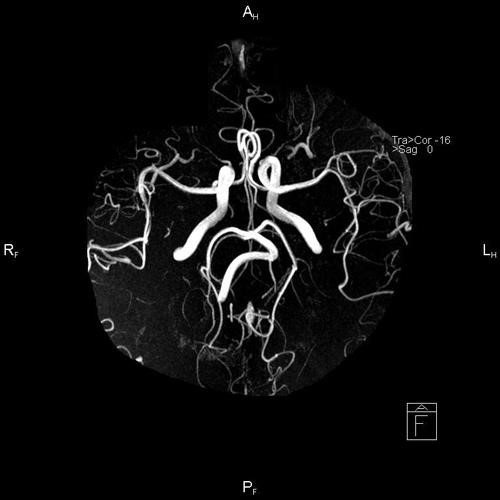

Ангиография позвоночных артерий при гипоплазии

Первым делом требуется первичный осмотр врачом-терапевтом, вертебрологом или сосудистым хирургом. На приеме врач соберет анамнез и проведет различные тесты (например, позу Ромберга ).

Следующим этапом является проведение ультразвуковой диагностики позвоночных артерий. Данный метод визуализации позволяет увидеть сужения или компрессию (сдавливание) сосудов, а также оценить скорость кровотока в них.

Наличие подозрений на гипоплазию по данным УЗИ – повод для проведения более точной и информативной диагностики. Для этого используется магнитно-резонансная томография в режиме ангиографии или компьютерная томография с контрастом.